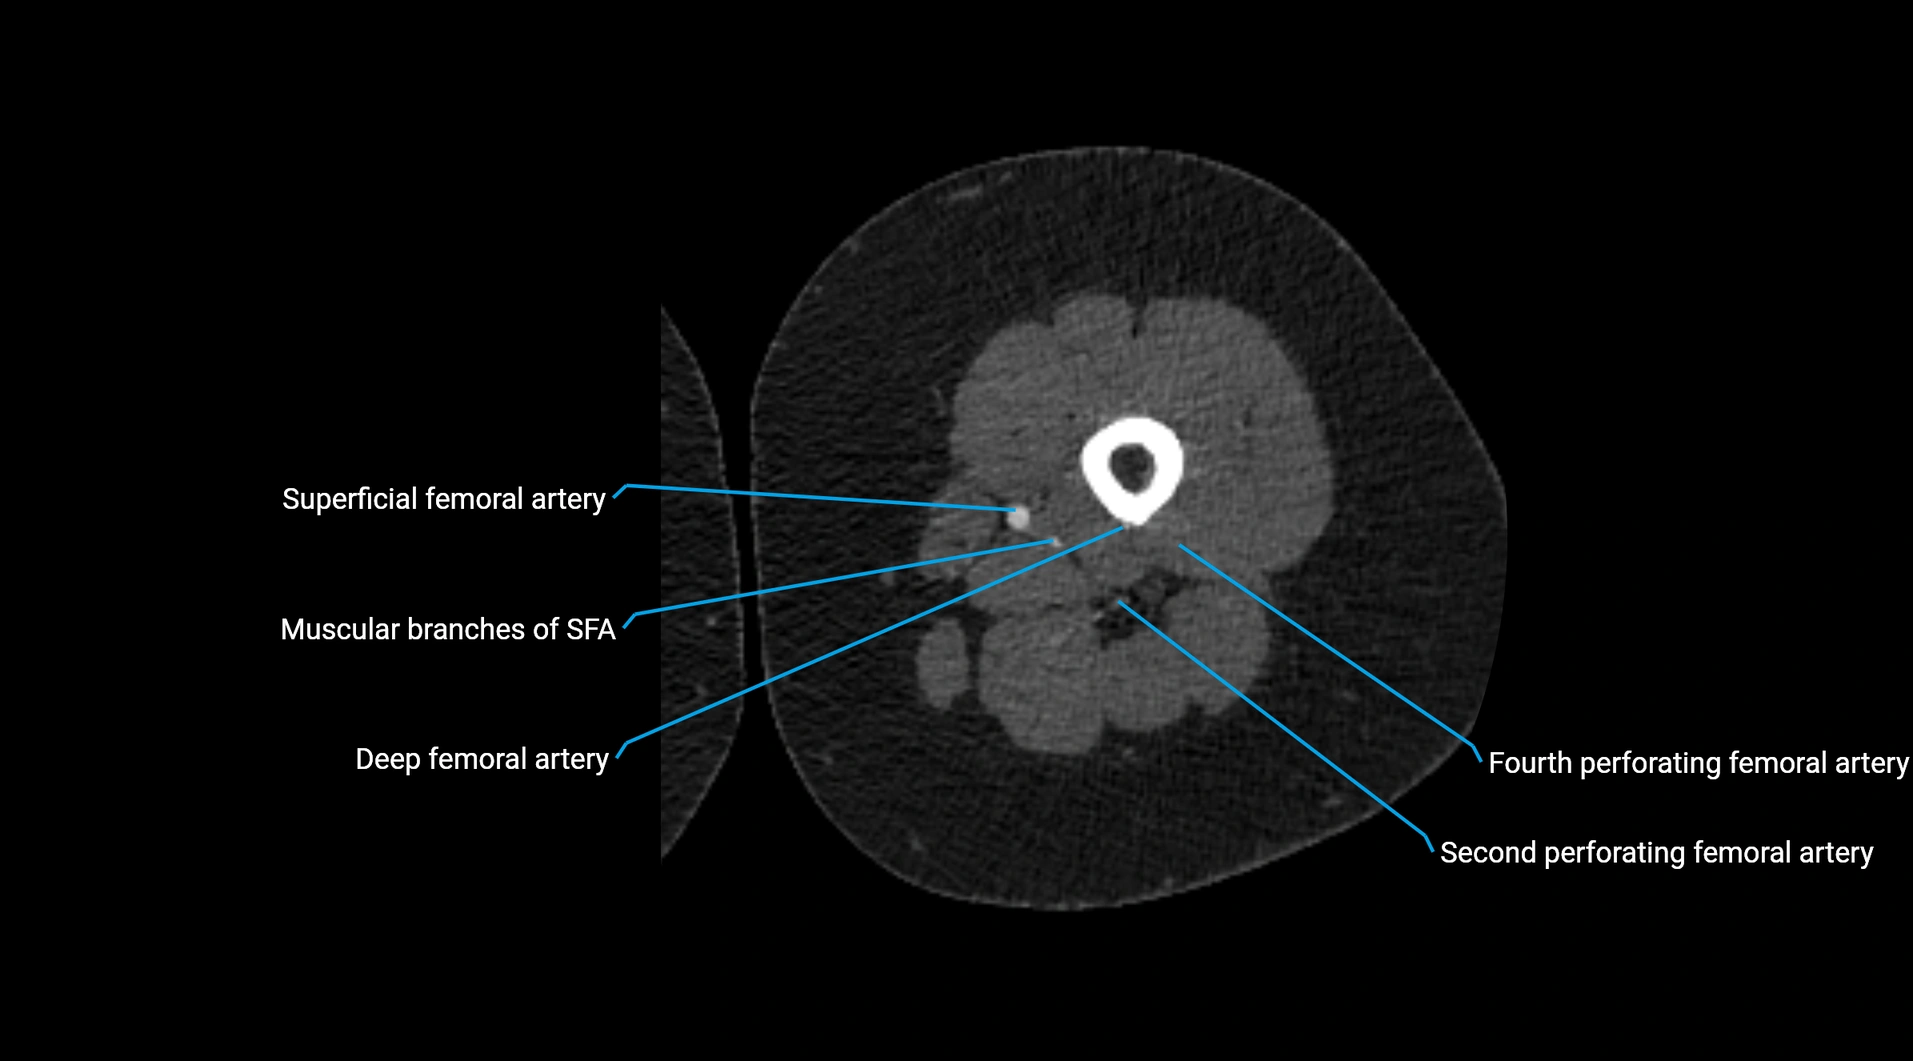

Contrast-enhanced CT (CTA):

• Gold standard for abdominal aortic imaging

• Provides excellent detail of lumen, wall, aneurysm, thrombus, and branch vessels

• Multiplanar and 3D reconstructions help in aneurysm measurement, stent graft planning, and dissection evaluation

• Detects acute rupture, traumatic injury, or occlusion with high sensitivity